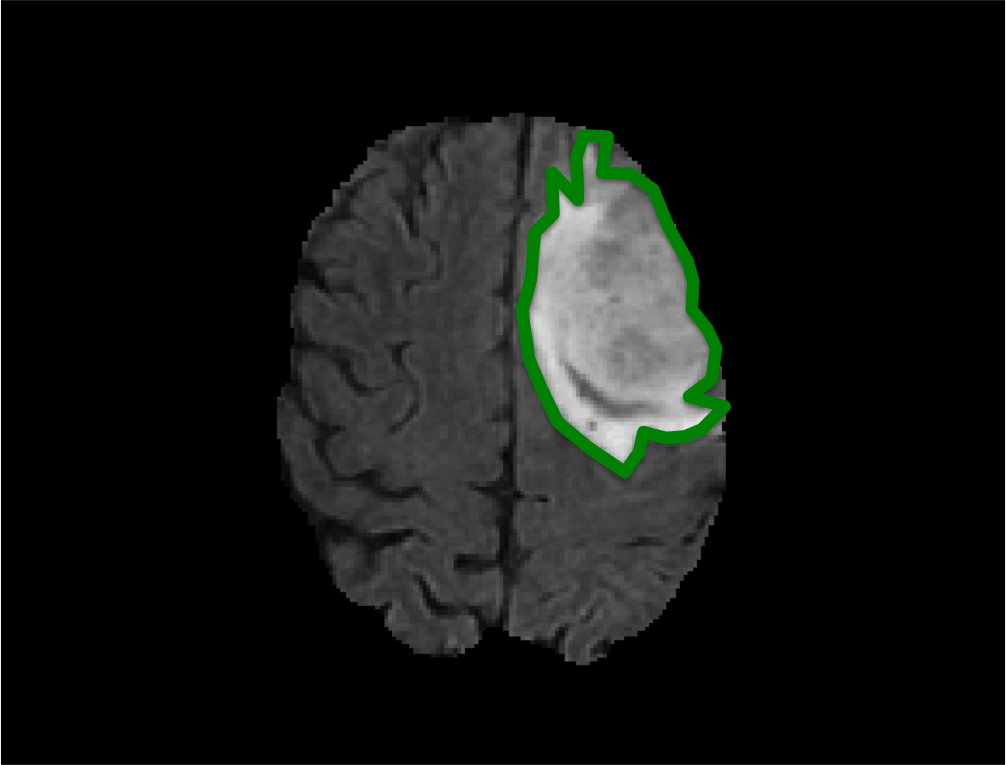

Ground truth annotations play a critical role in the development of machine learning methods in medical imaging. Indeed, advances in deep learning strategies, coupled with the advent of image data in medicine have greatly improved performances for tasks such as structure detection and anatomical segmentation across most imaging modalities (e.g. MRI, CT, Endoscopy, Microscopy) [6, 1]. Yet the process of acquiring ground truth data or annotations remains laborious and challenging, especially in video and 3D image data such as those depicted in Fig. 1.

We evaluated each of the above mentioned methods on 4 very different image sequences (see Fig. 1 for examples): (1) a 3D brain MRI containing a tumor to annotate from the BRATS challenge [10] consisting of 73 slices, (2) a 30 frame surgical video sequence from the MICCAI EndoVision challenge 111Endoscopic vision challenge: https://endovis.grand-challenge.org where a surgical instrument must be annotated, (3) a 95-slice 3D CT scan where a cochlea must be annotated and (4) a slit-lamp video recording (195 frames) of a human retina where the optic disk must be segmented. Pixel-wise annotated ground truth on all frames of each sequence was either available or produced by a domain expert. In all sequences, one and only one object is present throughout the sequence.